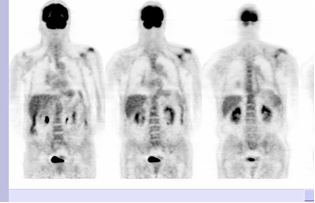

Maladie de Paget – TEP FDG

découverte fortuite d’une maladie de Paget de la scapula gauche.

Hypermétabolisme modéré de la scapula gauche qui apparait hypertrophiée, avec aspect ostéocondensé et remanié.

La maladie de paget peut mimer des métastases osseuses en TEP-FDG: la captation est variable mais dans la majorité des cas les atteintes osseuses pagétiques sont négatives en TEP-FDG.